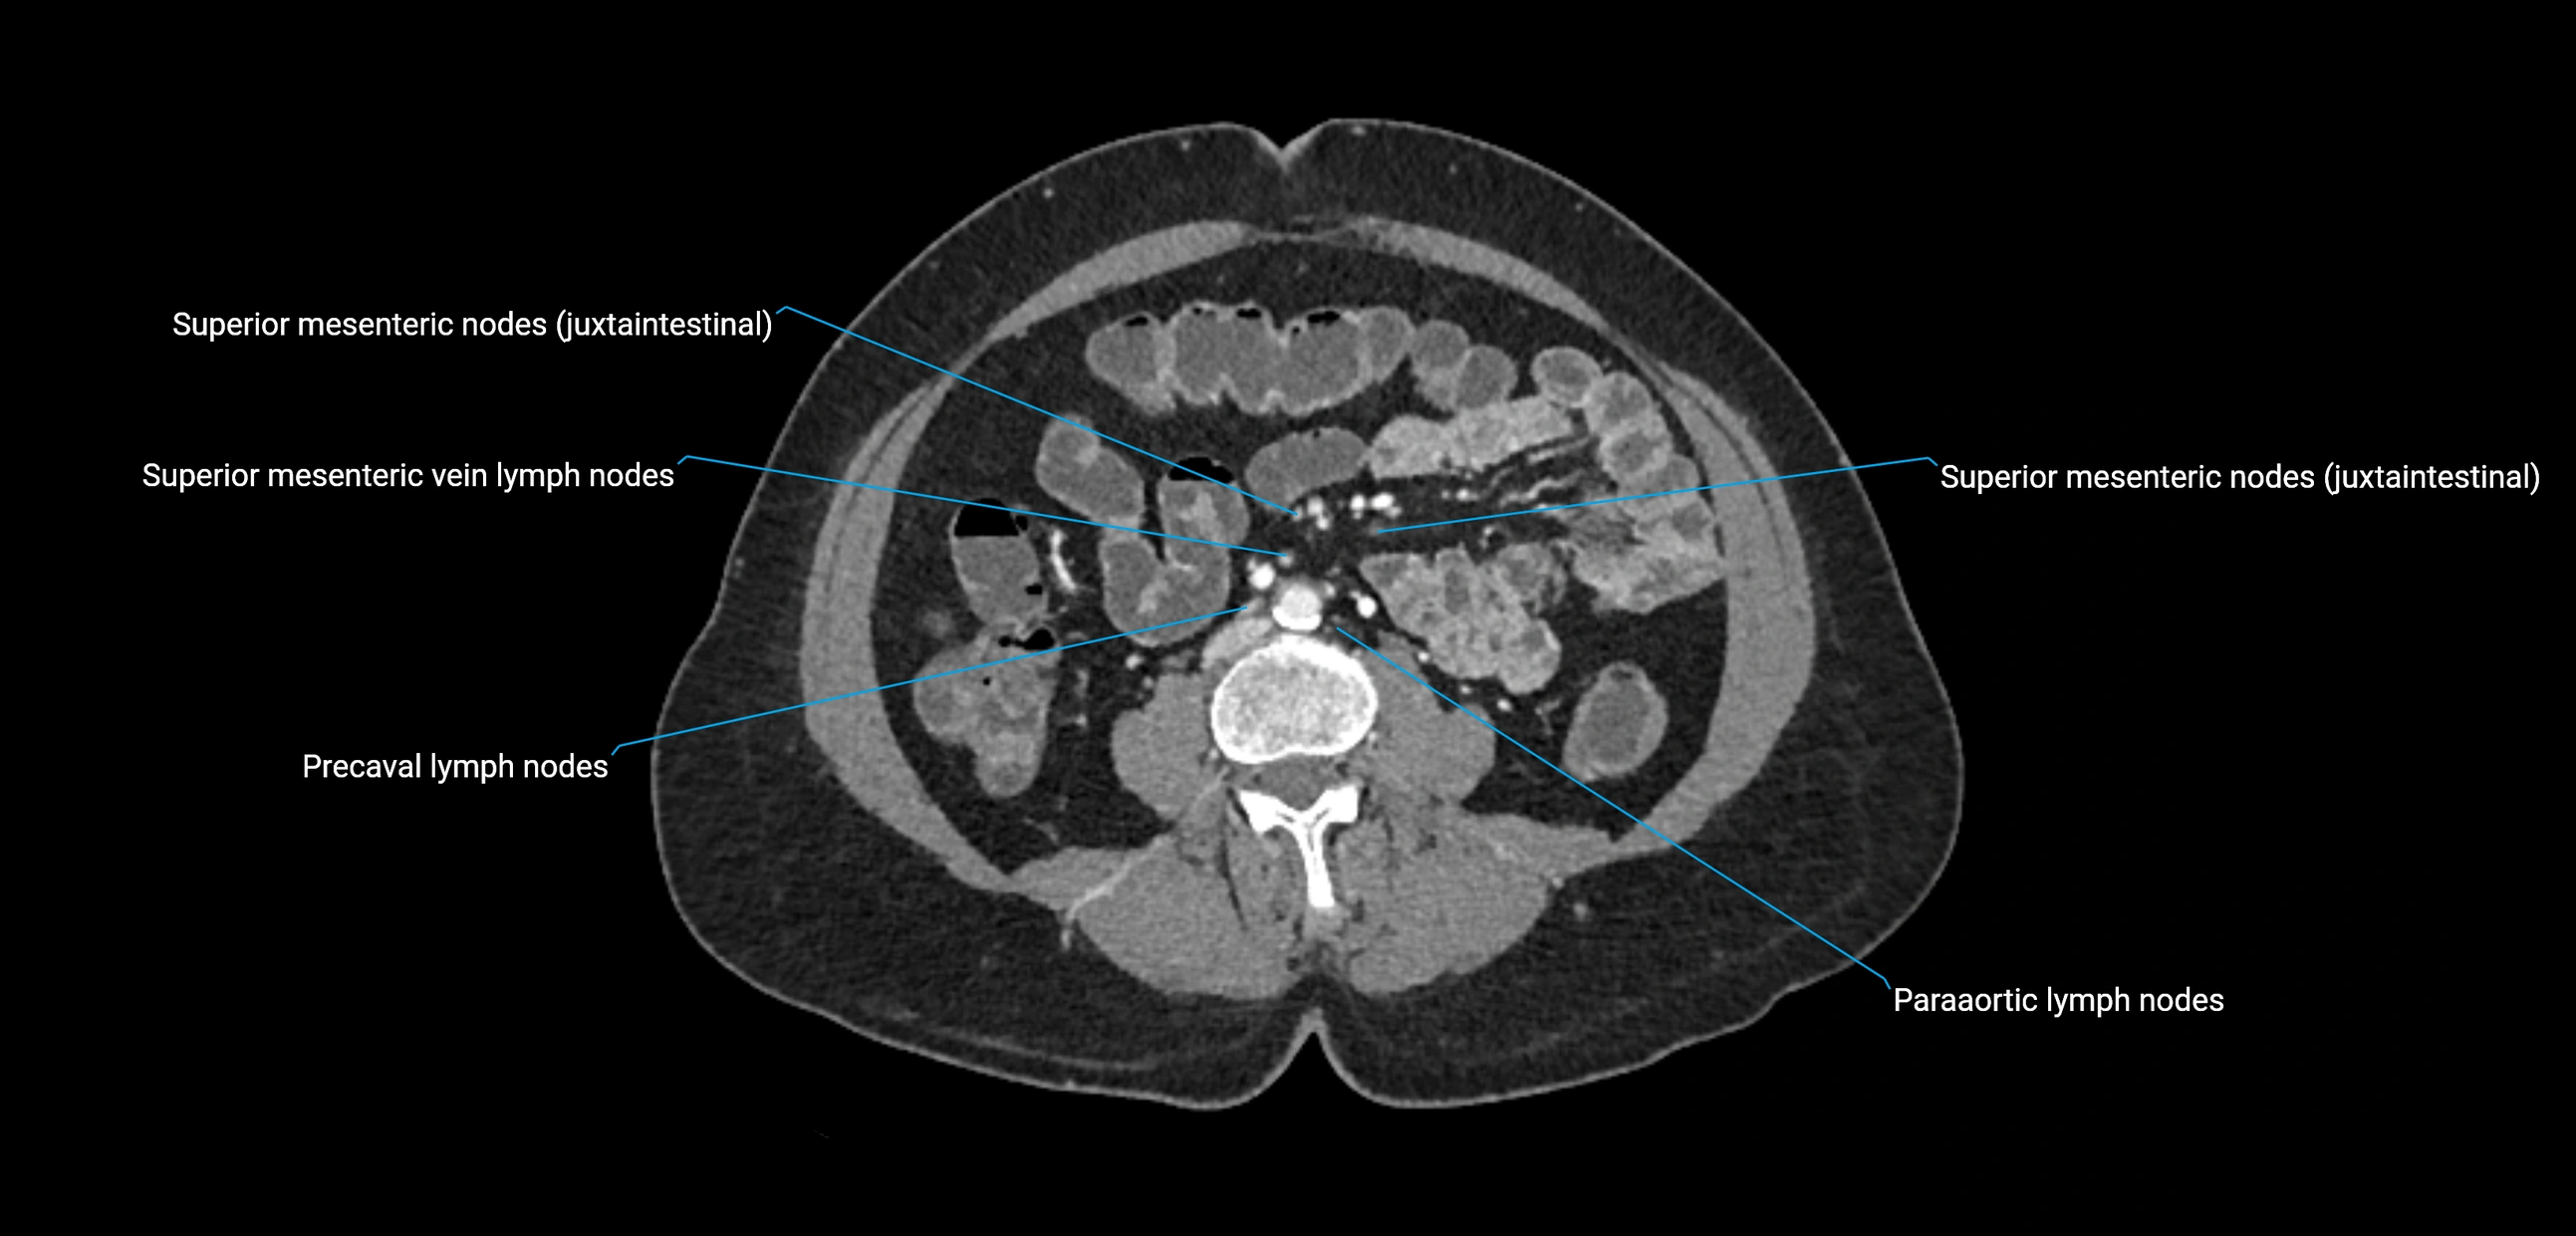

CT image

image